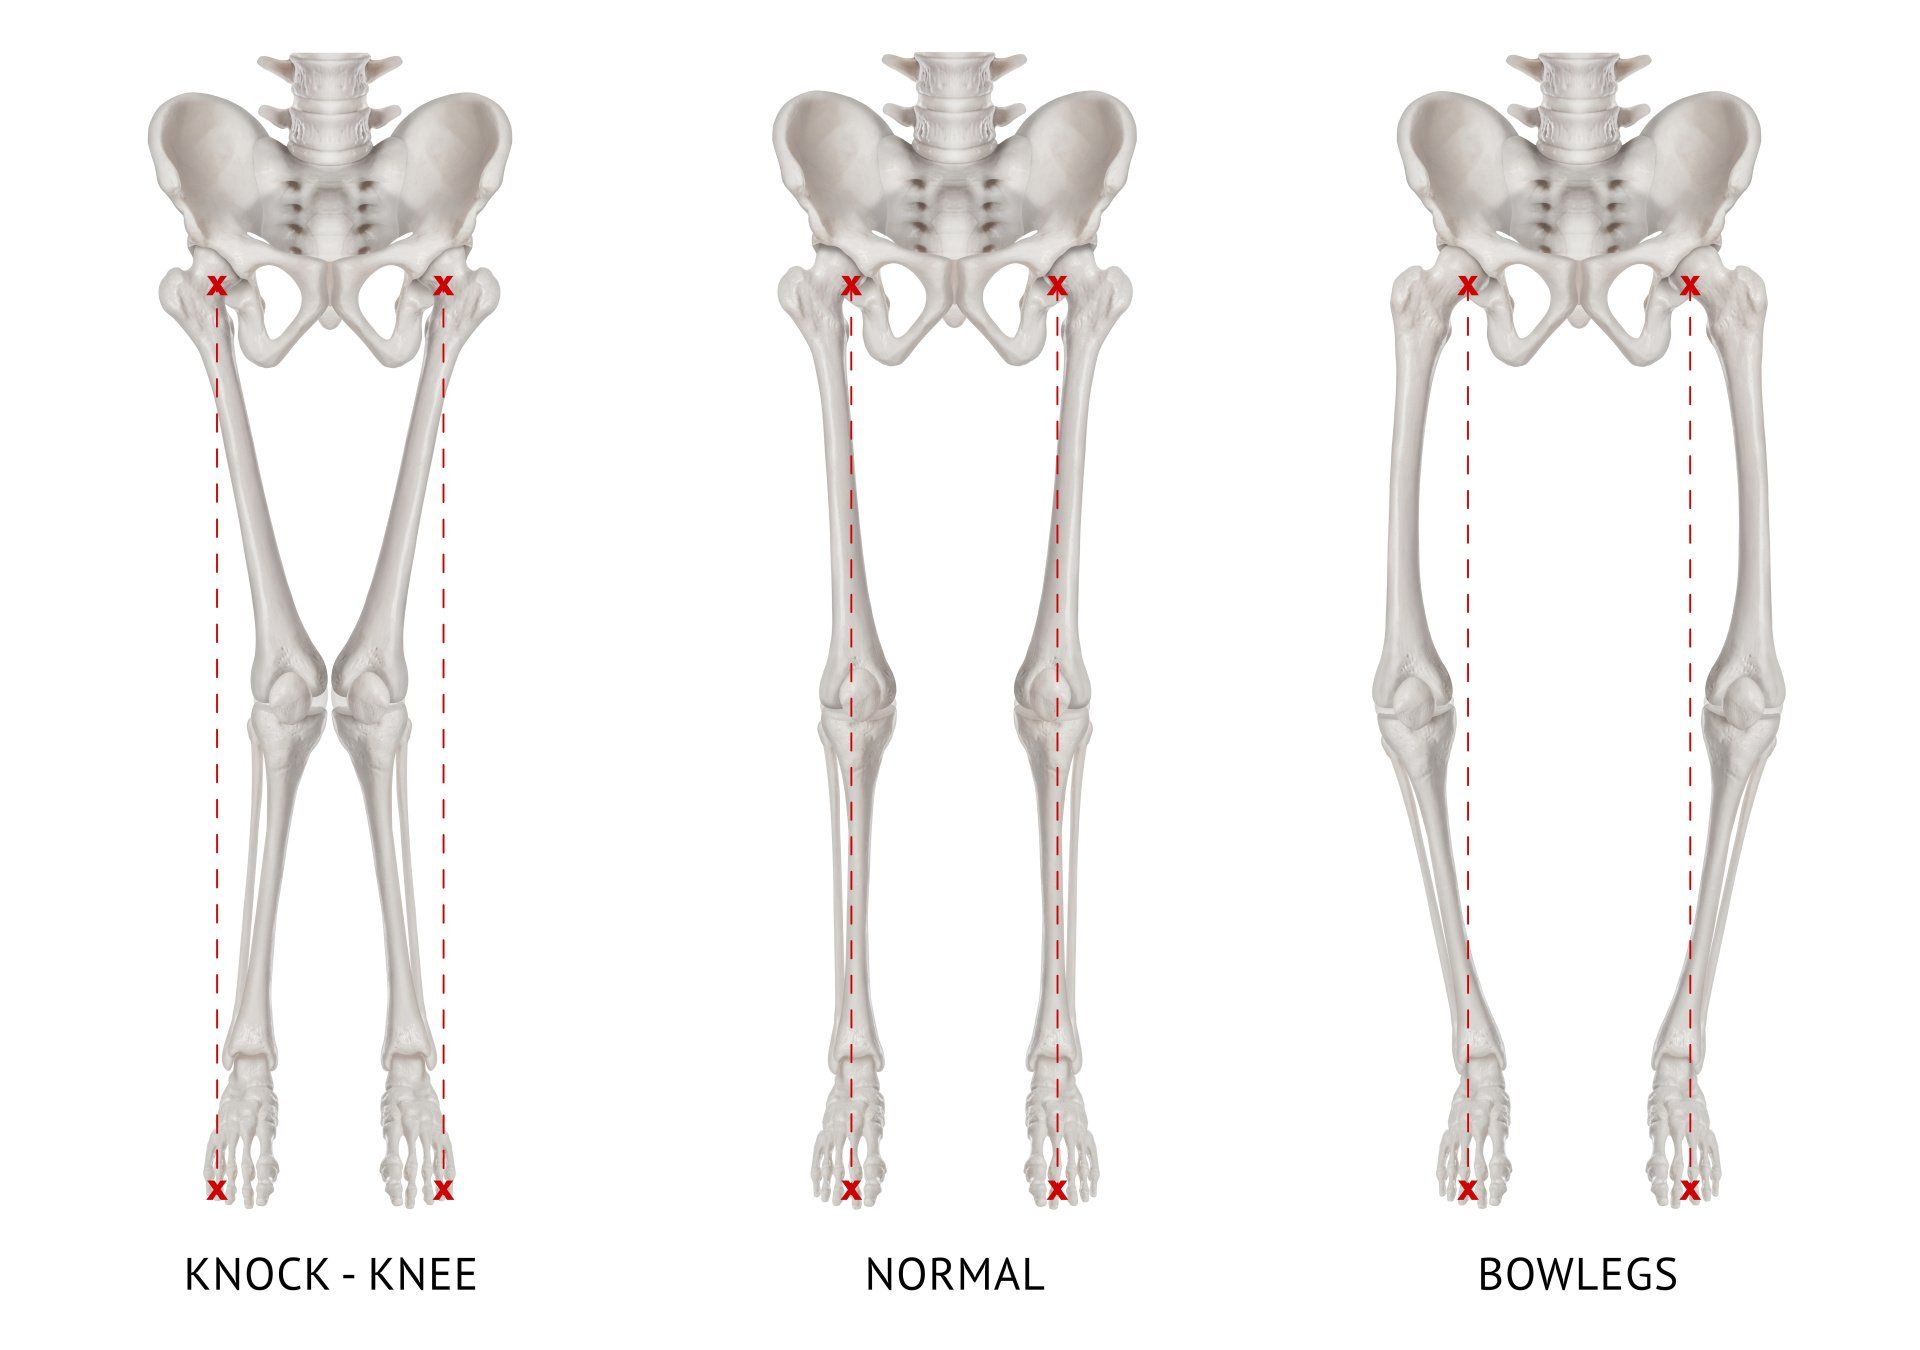

- Η γραμμή που φέρεται από το κέντρο του ισχίου στο κέντρο της ποδοκνημικής πρέπει να διασχίζει το μέσο του γόνατος:

- Αυτό ονομάζεται μηχανικός άξονας του κάτω άκρου και δείχνει που ασκούνται οι δυνάμεις στο γόνατο κατά την όρθια στάση

- Σε ένα τέτοιο σενάριο οι δυνάμεις κατανέμονται εξίσου στο γόνατο

Τι είναι η ραιβογονία;

- Όταν ο μηχανικός άξονας περνά στην εσωτερική πλευρά πάρα στο κέντρο του γόνατος, η ποδοκνημική βρίσκεται πιο κοντά και το γόνατο πιο μακριά στη μέση γραμμή του σώματος (κάθετη γραμμή ενώνοντας την μύτη και τον ομφαλό):

- Αυτό ονομάζεται παραμόρφωση του γόνατος σε ραιβότητα (ραιβογονία - ραιβό γόνατο)

- Ως αποτέλεσμα, περισσότερες δυνάμεις περνούν από την εσωτερική πλευρά του γόνατος, οδηγώντας σε πρώιμη ρήξη του μηνίσκου και του αρθρικού χόνδρου που οδηγεί σε οστεοαρθρίτιδα σε αυτή την πλευρά του γόνατος

- Είναι ο συνηθέστερος τύπος παραμόρφωσης του γόνατος γι’ αυτό και παρατηρείται οστεοαρθρίτιδα πιο συχνά και πιο έντονα στην έσω πλευρά του γόνατος

Τι είναι η βλαισογονία;

- Όταν ο μηχανικός άξονας περνά στην εξωτερική πλευρά πάρα στο κέντρο του γόνατος, η ποδοκνημική βρίσκεται πιο μακριά και το γόνατο πιο κοντά στη μέση γραμμή του σώματος (κάθετη γραμμή ενώνοντας την μύτη και τον ομφαλό):

- Αυτό ονομάζεται παραμόρφωση του γόνατος σε βλαισότητα (βλαισογονία - βλαισό γόνατο)

- Ως αποτέλεσμα, περισσότερες δυνάμεις περνούν από την έξω (εξωτερική) πλευρά του γόνατος, οδηγώντας σε πρόωρη βλάβη του μηνίσκου και του αρθρικού χόνδρου που οδηγεί σε οστεοαρθρίτιδα έξω διαμερίσματος

- Είναι λιγότερο συχνή από τη ραιβογονία

Ραιβογονία είναι η πιο συνηθισμένη διαταραχή ευθυγράμμισης γι’ αυτό και επηρεάζεται ποιος συχνά και πιο έντονα την έσω πλευρά του γόνατος